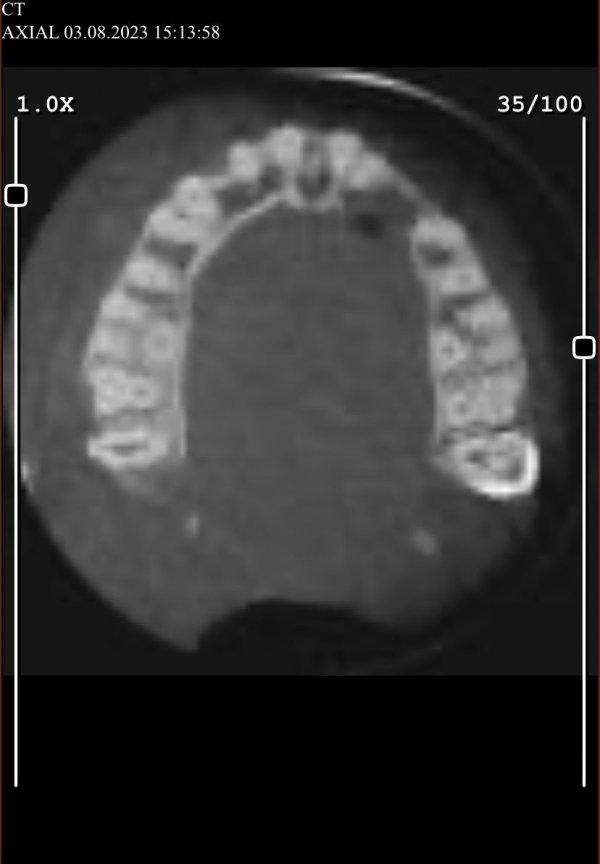

Nazilli ilçesinde yaşayan ve giyim sektöründe hizmet veren Esra Bulut, Temmuz ayında, diş tedavisi için ilçedeki bir kliniğe gitti ancak hayatının kabusunu yaşadı. Gömülü köpek dişi ameliyatı olan Bulut, operasyonda yaşadığı zorlukları Havadis Gazetesi’ne anlattı.

Kendisine burun sinüs zarının yırtıldığını, burun kanalından içeriye çekilen diş kök kemiğinin kaçtığını ve damağında 8.5 mm sinüsün kaldığını söylendiğini aktaran Bulut, “Şunu öğrendim ki, diş hekimlerinin bu ameliyatı yapmaya yetkisi yokmuş. Bu işlemin bir çene cerrahı tarafından yapılması gerekiyormuş. Şimdi bir kez daha ameliyat olmam gerekiyor.” ifadelerini kullandı.